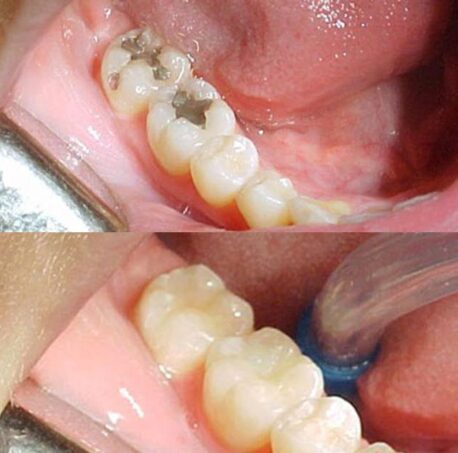

As restaurações dentárias estéticas são uma opção para corrigir imperfeições nos dentes, com objetivo de melhorar a aparência e a função dental. Elas podem ser feitas com diferentes materiais, como resina composta, porcelana e zircônia. A resina composta é o material mais comum para restaurações estéticas. É um material versátil que pode ser moldado diretamente na boca do paciente, oferecendo resultados de boa qualidade em casos de cáries pequenas, fraturas dentárias ou desgaste do esmalte. A resina composta também é mais barata em comparação com outros materiais de restauração.

Uma restauração estética é um procedimento odontológico que visa melhorar a aparência dos dentes, corrigindo imperfeições estéticas, como manchas, descolorações, dentes lascados, fraturados ou com formato irregular. Essas restaurações podem ser feitas com materiais como resina composta ou porcelana.

As facetas de porcelana são lâminas finas feitas de porcelana que são colocadas na parte frontal dos dentes para melhorar sua aparência. Já as restaurações de resina composta são feitas de um material compósito de resina que é moldado e esculpido diretamente nos dentes. Ambos os materiais têm suas próprias características e benefícios.